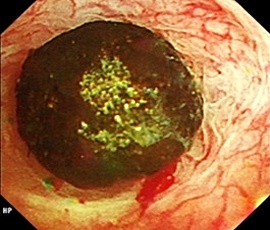

手術画像(胆道鏡)